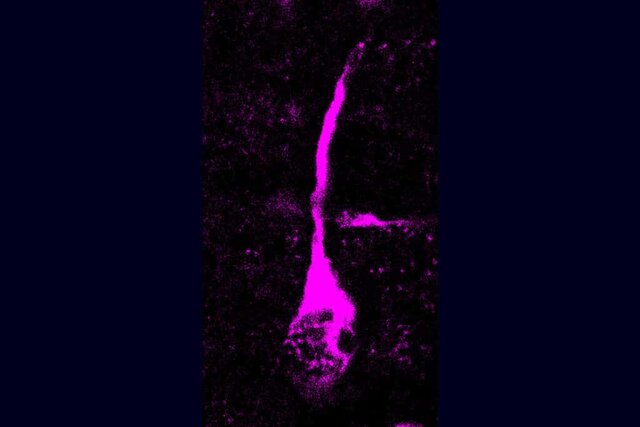

دانشمندان موسسه بیولوژی سلولی مولکولی و ژنتیک ماکس پلانک (MPI-CBG) در درسدن آلمان در جدیدترین مطالعه، اثر یک تغییر اسید آمینه منفرد در پروتئین ترانسکتولاز مانند ۱ (TKTL۱) را بر تولید گلیای شعاعی پایه که بخش زیادی از نئوکورتکس را تولید میکند، تجزیه و تحلیل کردند. آنها دریافتند که نوع پروتئین TKTL۱انسان مدرن که تنها یک اسید آمینه با نوع نئاندرتال متفاوت است، یک نوع از سلولهای پیش ساز مغز به نام گلیا شعاعی پایه را در مغز انسان مدرن افزایش میدهد.

بخش عمدهای از نورونها در نئوکورتکس در حال رشد، (ناحیهای از مغز که برای بسیاری از عملکردهای شناختی ضروری است) توسط سلولهای گلیال شعاعی پایه تولید میشوند. دانشمندان پس از بررسی به این نتیجه رسیدند که این جایگزینی اسید آمینه اختصاصی برای انسان در TKTL۱ زمینهساز تولید نورون بالاتری در قشر قدامی در حال رشد نئوکورتکس در انسانهای امروزی نسبت به نئاندرتالها است، زیرا فعالیت TKTL۱ بهویژه در قشر قدامی مغز انسان جنین بالاست.

دانشمندان در گام بعد، اهمیت این تغییر اسید آمینه را برای رشد نئوکورتکس بررسی کردند. آنها TKTL۱ انسان مدرن یا نوع نئاندرتال را وارد نئوکورتکس جنینهای موش کرده و مشاهده کردند که سلولهای گلیال شعاعی پایه، نوعی از اجداد نئوکورتیکال که گمان میرود نیروی محرکه برای مغز بزرگتر هستند)، با نوعTKTL۱ انسان مدرن افزایش یافته است، اما در نئاندرتالها اینگونه نبوده است. در نتیجه، مغز جنینهای موش با TKTL۱ انسان مدرن حاوی نورونهای بیشتری بود.

در ادامه، پژوهشگران به بررسی این موضوع پرداختند که این اثرات چقدر برای رشد مغز انسان قابل توجه است. برای دستیابی به این هدف، آنها از ارگانوئیدهای مغز انسان استفاده کردند تا آرژنین موجود در TKTL۱ انسان مدرن را جایگزین ویژگی لیزین TKTL۱ نئاندرتال کنند.

پژوهشگران این مطالعه تأکید کردند: دریافتیم که با اسید آمینه نوع نئاندرتال TKTL۱، سلولهای گلیال شعاعی پایه کمتری نسبت به نوع انسان مدرن تولید میشود و در نتیجه، نورونهای کمتری نیز تولید میشود. این به ما نشان میدهد که حتی اگر نمیدانیم مغز نئاندرتال چند نورون دارد، میتوانیم فرض کنیم که انسانهای امروزی نورونهای بیشتری در قشر قدامی مغز دارند.